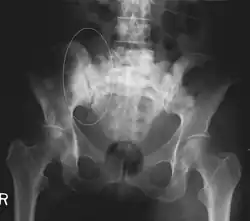

| 3D rendered CT scan of bone metastases of the hip bone, in a 60 year old woman with parotid gland cancer. Large lesions are seen on the ilium on the more distant side. Involvement of the vertebral column has caused a compression fracture. | |